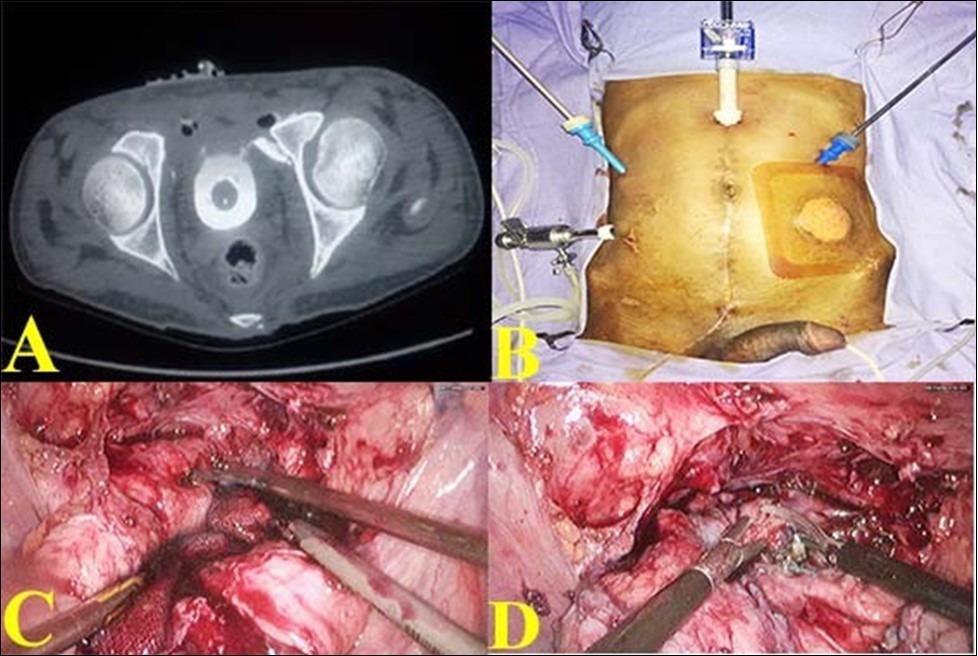

17-year-old male was referred with a urethral and suprapubic catheter and complaints of fever and pyuria for 6 weeks. The prior record showed that he was admitted 2 months earlier following a road traffic accident with pain in the lower abdomen, hematuria and anal tear. He was initially stabilized and was evaluated with a CT scan which showed a pelvic fracture; extra-peritoneal bladder injury at two sites in the antero-lateral wall. The attending trauma surgeon did diverting colostomy for anal tear and supra-pubic cystostomy. Patient was referred after 6 weeks of fever and pyuria. Clinical examination revealed fair general condition and abdomen examination revealed a well-healed midline laparotomy scar along with colostomy, supra-pubic and urethral catheters. Bio-chemical investigation revealed normal renal function. Urine culture was positive and he was treated with culture specific antibiotic as he was symptomatic. After 7 days of treatment, computerized tomographic cystogram was done, which showed bilateral extra peritoneal bladder tears of about 15mm in length with extravasation of contrast from the anterolateral wall of bladder close to bladder neck bilaterally. Figure 1(A). Considering the persistence of gross extravasation of bladder contrast even after 7 weeks; laparoscopic repair of the bladder rent was planned.

Sigmoid colostomy was covered with sterile adhesive. With the patient in supine position, using 4 ports, laparoscopy was done. Figure 1 (B). There were extensive omental and bowel adhesions, which were released. Bladder was dropped and the SPC was removed. Extensive fibrosis was noted between the anterior wall of the bladder and pubic bone. Further mobilization of anterior wall of bladder revealed a bone spicule impinging on the left anterolateral wall and causing a rent of about 15 mm. The other rent was noticed on the right anterolateral wall close to the bladder neck about 15 mm long. Figure 1 (C). The bone spicule was removed.

Diluted methylene blue solution was instilled through urethral catheter to confirm that there were no other rents. The two rents were connected and made into a single large rent. Figure 1 (D). The edges were trimmed and closed using 3-0 absorbable barbed suture and omentum was tacked over the suture line.

Figure 1.A. Pre-operative CT showing contrast extravasation in anterior wall with bony spicule; B. Port Placement for bladder repair; C. Bladder rent identified by methylene blue; D. Two defects joined into a single cystotomy